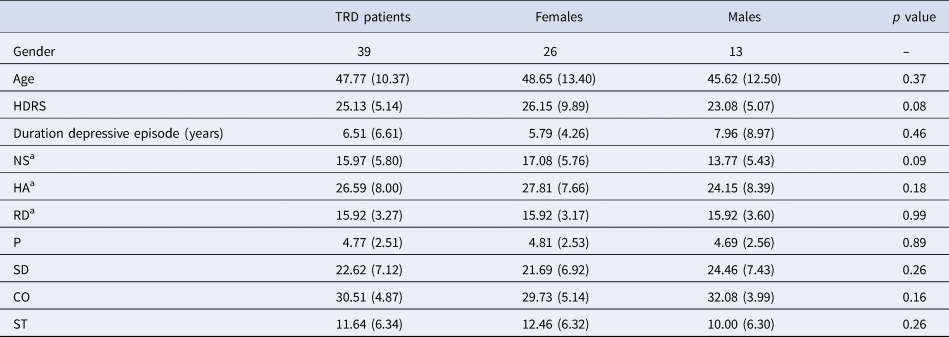

All behavioral data were analyzed with SPSS 25 (Statistical Package for the Social Sciences, IBM, Chicago, USA). The significance level was set at p ⩽ 0.05, two-tailed, for all analyses (see Table 1).

Table 1. Demographics

MDD, major depressive disorder; HDRS, Hamilton Depression Rating Scale; NS, novelty seeking; HA, harm avoidance; RD, reward dependence; P, persistence; SD, self-directedness; CO, cooperativeness; ST, self-transcendence.

Ratio's, means and standard deviations are provided.

a Temperament dimensions focused on for this study.